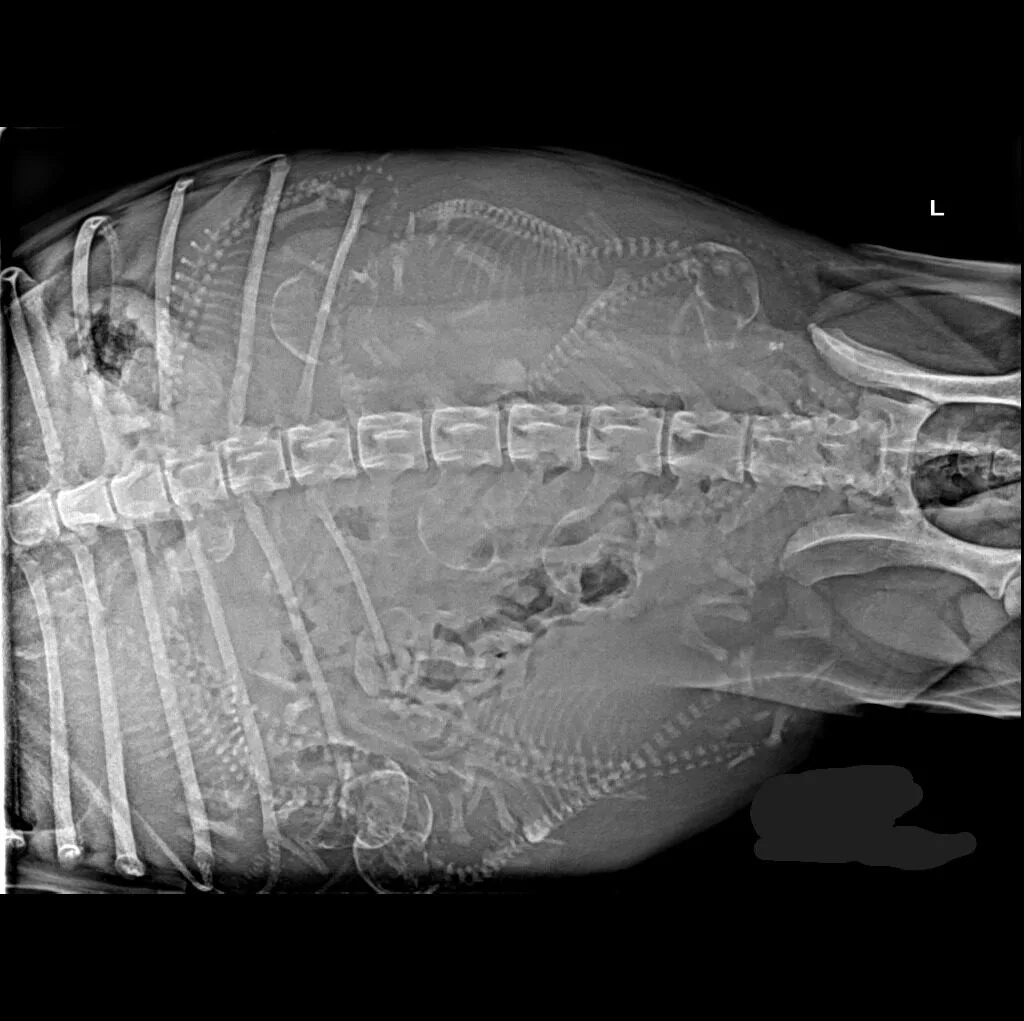

At Grand Ave. Pet Hospital, we utilize digital radiography to diagnose and monitor a wide range of medical conditions in pets. Digital X-rays provide clearer images, faster results, and safer radiation levels, ensuring the best possible care for your furry companion.

Digital radiography offers superior imaging quality and precision compared to traditional X-ray techniques. It allows us to detect hidden health issues early, leading to faster and more effective treatments.

🔹 Lameness & Joint Issues – Identifying fractures, arthritis, and mobility concerns

🔹 Cardiac & Respiratory Conditions – Evaluating heart disease and lung disorders

🔹 Abdominal & Gastrointestinal Issues – Detecting obstructions, tumors, or organ abnormalities